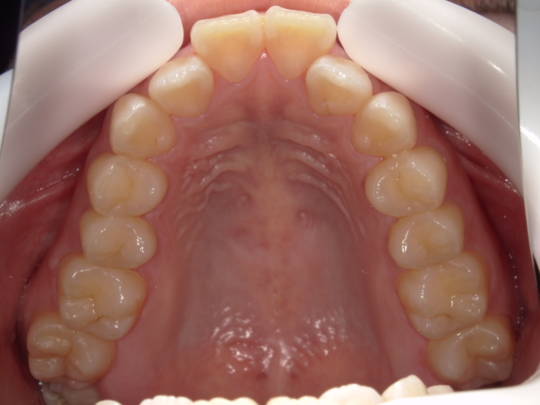

症例写真②

矯正前(正面)

矯正後(正面)

治療説明 歯科矯正でも目立ちにくい矯正方法です。透明に近いマウスピース型の矯正装置(アライナー)のため、歯に装着しても目立つことなく歯並びを矯正することが出来ます。また、一人ひとりの合わせて矯正装置を作製いたします。

治療期間 7か月

治療費用300,000 円

治療の副作用(リスク)歯の動き方には個人差があり、予想された治療期間が延長する可能性があります。。マウスピースの使用状況、矯正歯科治療には患者さんの協力が必要であり、それらが治療結果や治療期間に影響します。